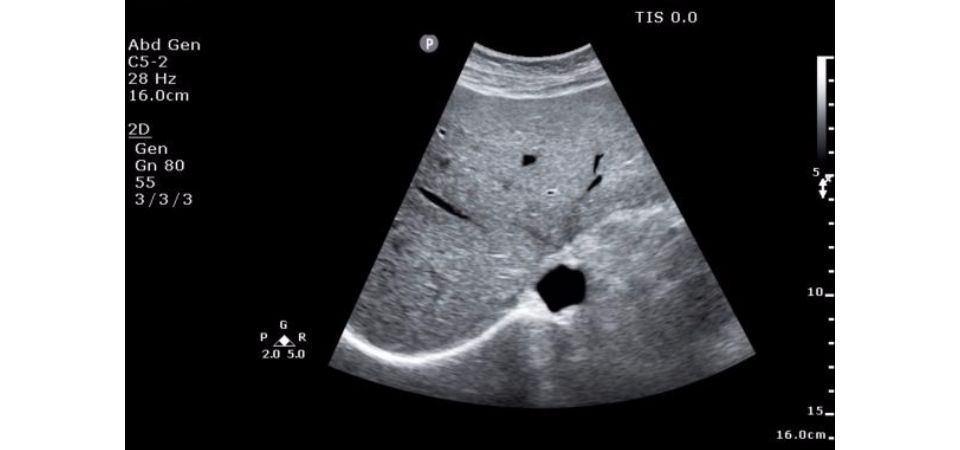

Philips ClearVue 850 – это мощная и продвинутая ультразвуковая система, которая предлагает широкий спектр возможностей для визуализации и обеспечивает высокую эффективность работы в любом отделении. Она оснащена передовыми технологиями и функциями, которые позволяют получать высококачественные изображения и диагностическую информацию.

УЗИ аппарат Philips ClearVue 850 обладает рядом основных характеристик, которые обеспечивают высокую технологичность и улучшают рабочие процессы:

• Высокое качество изображений: Система предлагает максимальное разрешение и четкость изображений, что позволяет врачам получать детальную диагностическую информацию.

Общая визуализация:

Да